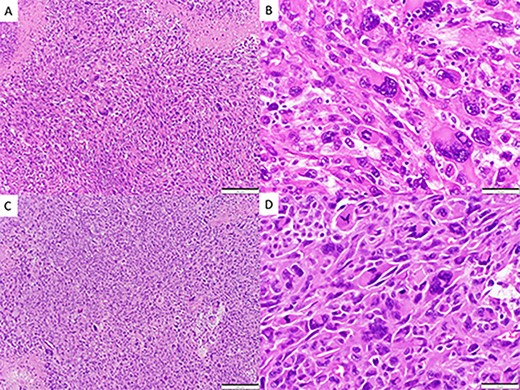

CASE

Postoperative CT and MRI scans of the head indicating complete tumor resection with reduced midline shift.